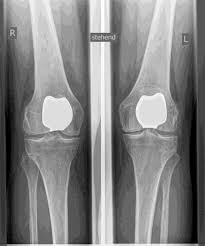

يشار إلى مفاصل الركبة الاصطناعية بالأطراف الاصطناعية الكاملة والأطراف الاصطناعية الجزئية. أتحقق بعناية مسبقًا من الطرف الاصطناعي المناسب لك بناءً على الفحص السريري، وكذلك على أساس صور الأشعة السينية أو التصوير بالرنين المغناطيسي.

- استبدال كامل للسطح الأسمنتي (الكلاسيكي: " الركبة الاصطناعية ")

يظل العظم الأساسي في عظم الفخذ والرأس الظنبوبي سليمًا. يقارن البعض مفصل الركبة الاصطناعي الحديث بتتويج الأسنان، والمصطلح الدقيق هو ما يسمى

إعادة تسطيح اللقمتين. بين الأسطح الجديدة في الجزء العلوي والسفلي من الساق يوجد ما يسمى بالبطانة المصنوعة من البلاستيك الأبيض المقوى خصيصًا، والتي يمكن رؤيتها في صورة الأشعة السينية على أنها المسافة بين الأجزاء المعدنية.